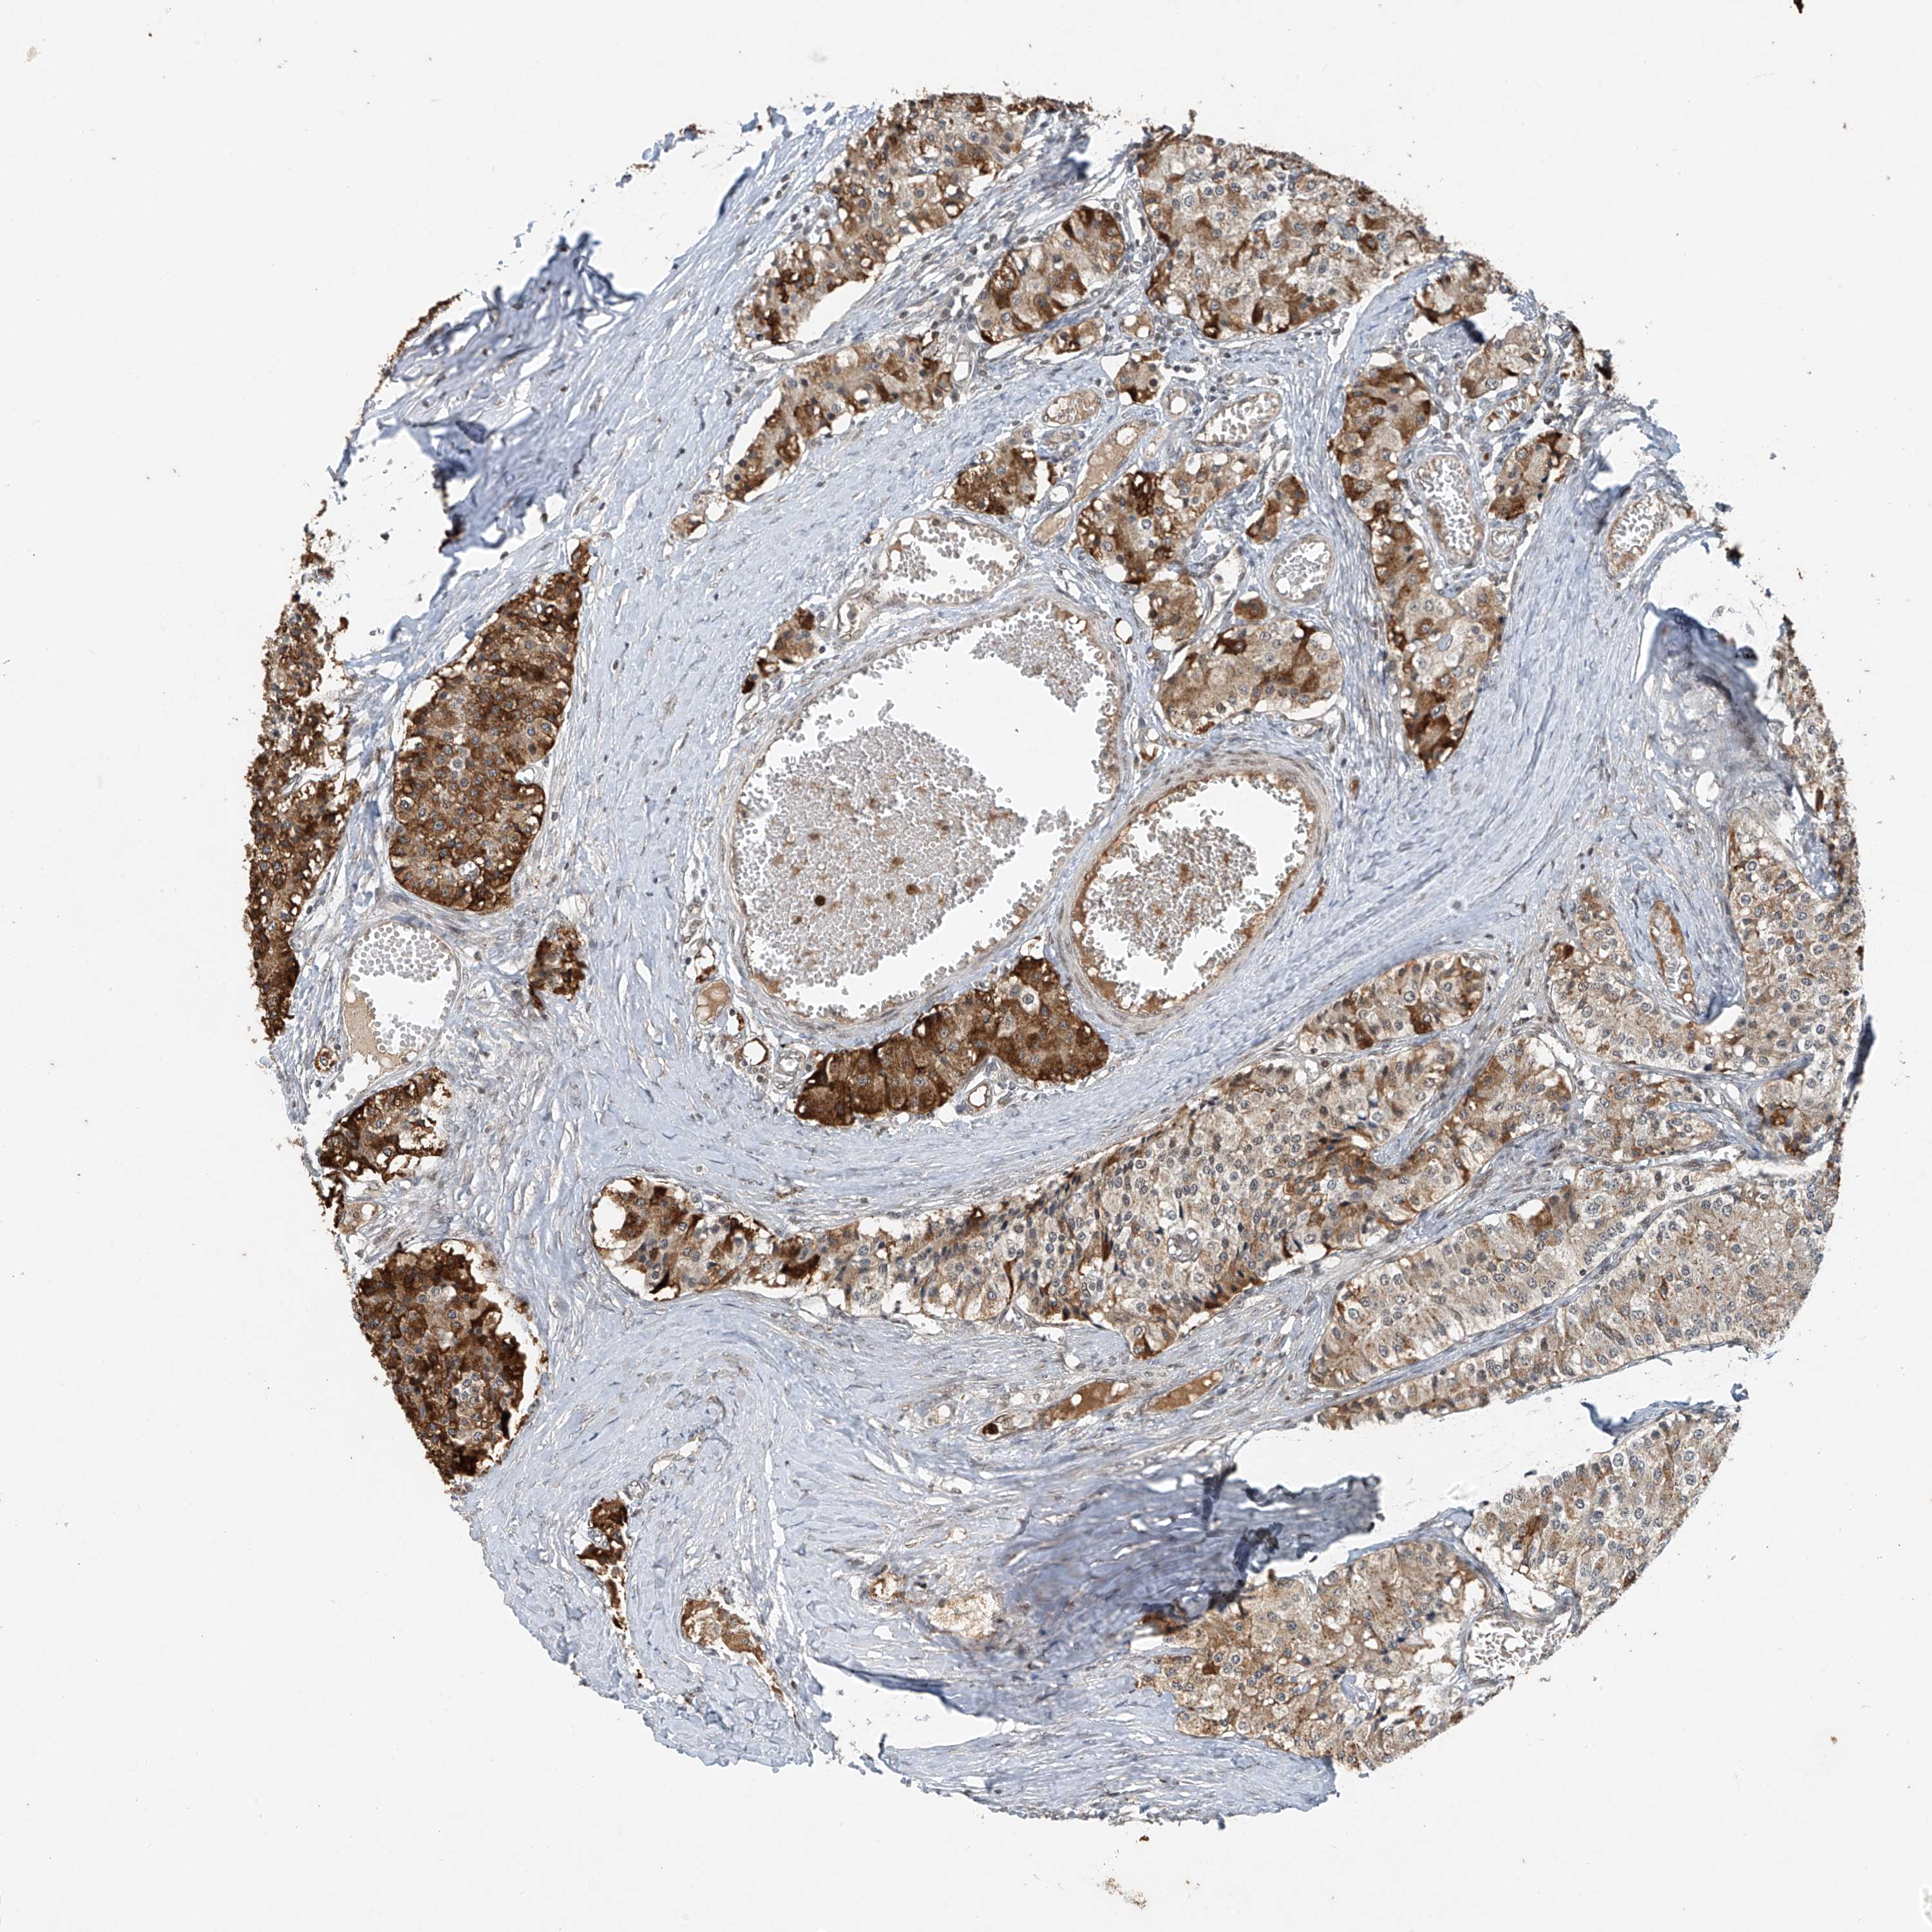

CARCINOID - Protein expressioni

A mouse-over function shows sample information and annotation data. Click on an image to view it in a full screen mode. Samples can be filtered based on level of antibody staining by selecting one or several of the following categories: high, medium, low and not detected. The assay and annotation is described here.

Antibody stainingi

Antibody staining in the annotated cell types in the current human tissue is reported as not detected, low, medium, or high, based on conventional immunohistochemistry profiling in selected tissues. This score is based on the combination of the staining intensity and fraction of stained cells.

Each image is clickable and will lead to virtual microscopy that enables deeper exploration of all samples and also displays staining intensity scores, fraction scores and subcellular localization as well as patient and tissue information for each sample.

Antibody HPA031730

Antibody HPA031731

Antibody HPA031734

Staining

High

Medium

Low

Not detected

Carcinoid, malignant, NOS